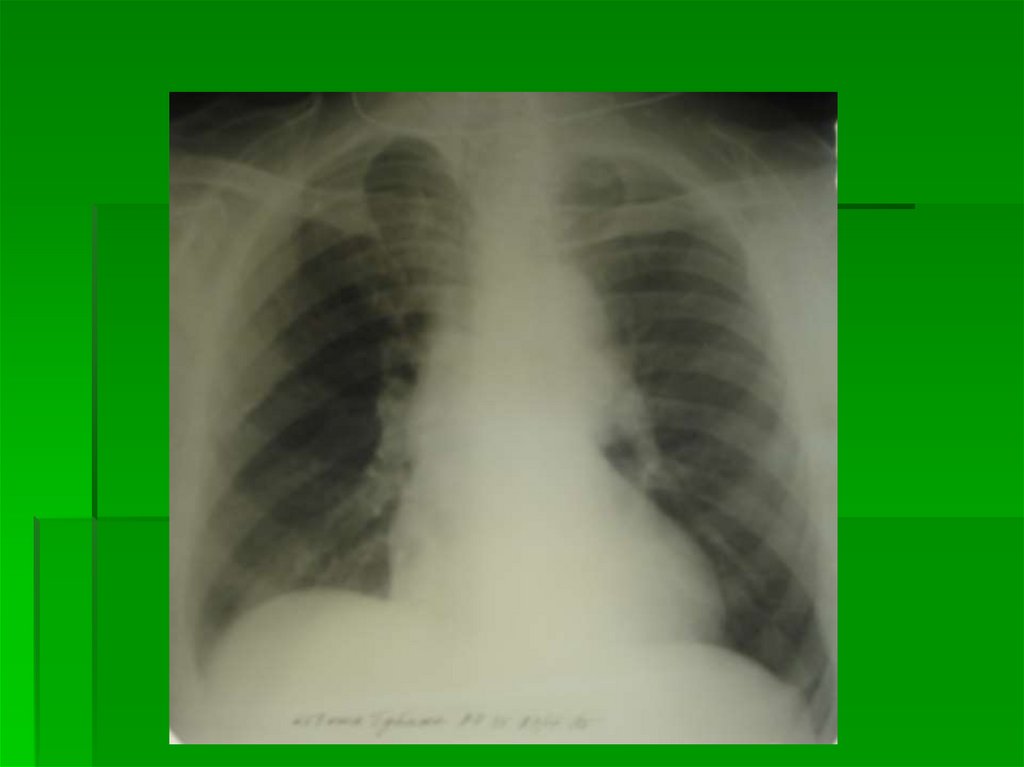

4 степень

Альвеолярный отек легких

Инфильтративно-подобный отек легких

Ограниченное затемнение в пределах

нижнего или среднего и нижнего легочного

поля, может быть односторонний

Дифференциальной диагноз – с пневмонией:

Оценить состояние МКК (Rn-признаки ЛВГ)

Обратная динамика за сутки